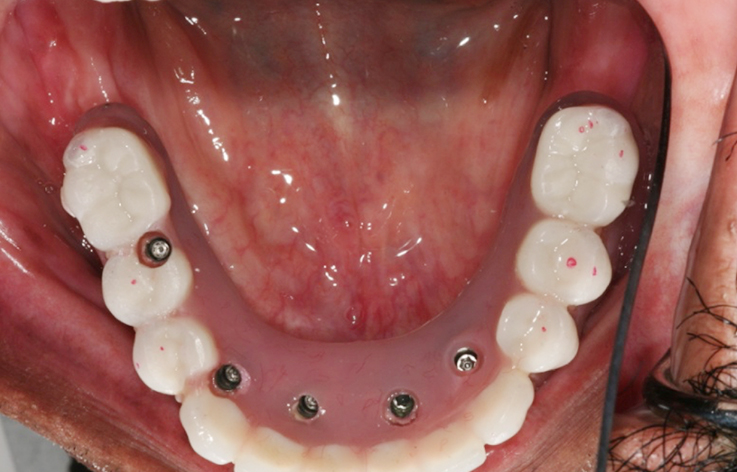

Implants/Bone Grafting

Fully edentulous clinical cases